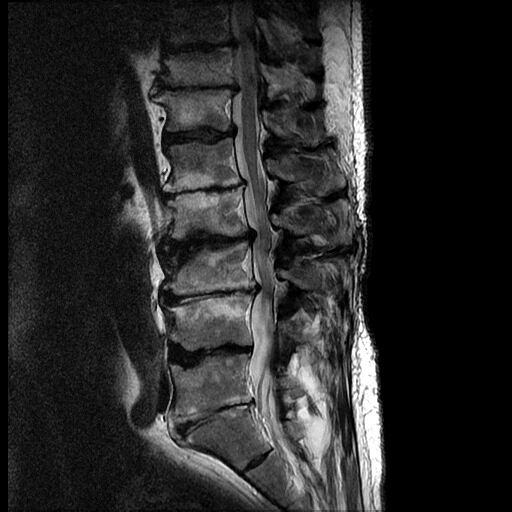

A black and white MRI scan of the human lumbar spine showing vertebrae, intervertebral discs, and spinal cord in a side view.

This scan shows degeneration of the lower 4 lumbar discs. The water content is reduced, so the nucleus is darker. The disc height is reduced leading to bulging (similar to when a tyre bulges when some air is let out). There are tiny white specks in the posterior margins of the discs which are annular fissures (degenerative splits).